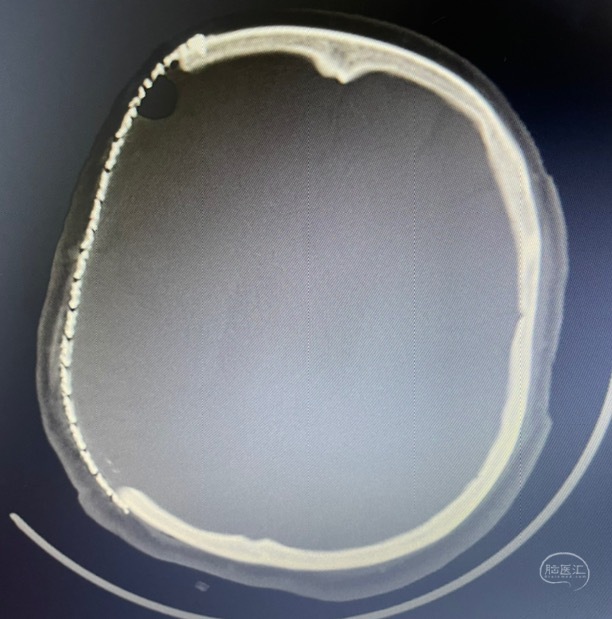

术后第一天复查

术后一月复查